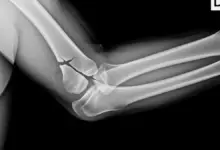

As radiografias em incidência anteroposterior e perfil costumam ser o primeiro exame. Só que, em fraturas sem desvio, o traço pode não aparecer.

Quando existe dúvida sobre quantidade de fragmentos, grau de desvio e planejamento cirúrgico, a tomografia costuma ser o exame mais útil.